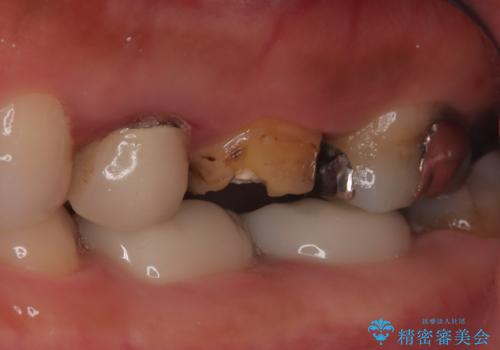

【破折ファイル除去】他院で折れた根管治療の器具をとってほしい

- 他院で折れた根管治療の器具をとってほしいという主訴で来院されました。

マイクロスコープで根管内を観察すると、除去できる状態だったため破折ファイル除去を行いオールセラミッククラウンにて修復治療しております。

- 35万円費用は治療当時の料金となります